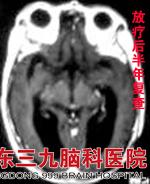

考虑到陈婆婆为颅内单发病灶,且病灶较大,专家建议其先接受手术治疗,但陈婆婆的家人考虑到她年纪较大,遂拒绝手术治疗。为减轻陈婆婆的症状,肿瘤综合治疗中心蔡林波主任决定先为其行分次X刀治疗。因患者病理EGFR突变阳性,同步开始易瑞沙靶向治疗,X刀治疗后行全脑放射治疗。治疗后陈婆婆症状明显改善,头痛等不适消失。www.999brain.com

近日陈婆婆回院复查,见头部病灶已完全消失,肺部病灶明显消退,陈婆婆精神状态良好,无不适症状。